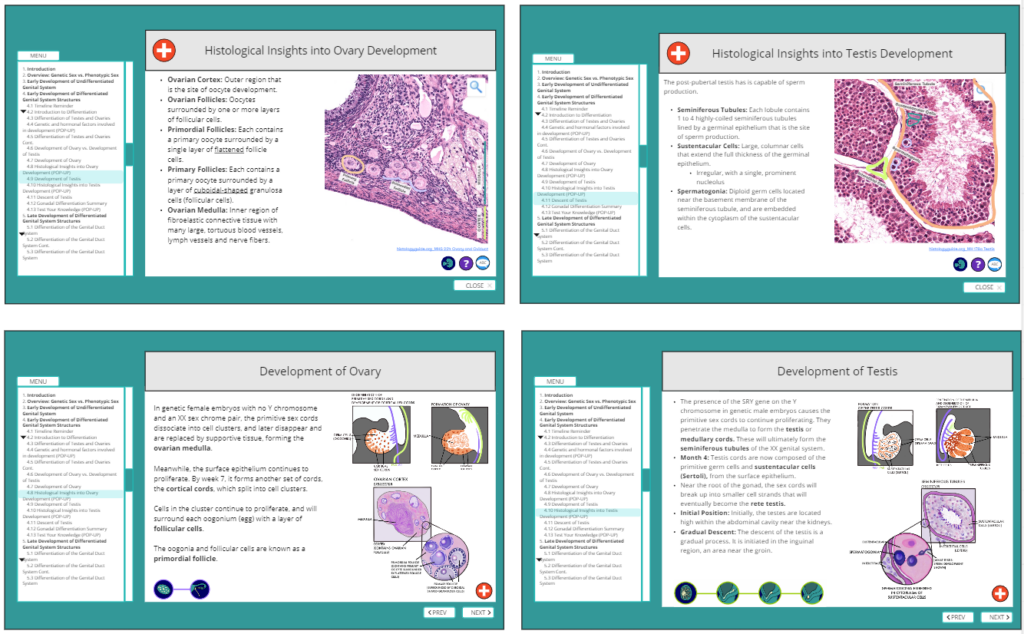

This project, a collaboration between Dr. Valerie O’Loughlin (Indiana University) and my Biomedical Communications capstone team at the UBC HIVE, reimagines how genital embryology is taught. Our goal was to address outdated binary constructs and integrate the latest scientific research into a visually engaging, accessible, and inclusive learning experience for students and educators alike.

Traditional embryology education often oversimplifies genital system development, relying on binary models that fail to reflect biological diversity. Our interactive module addresses this gap, offering a comprehensive, research-backed exploration of genital development with a focus on inclusivity and scientific accuracy. This approach promotes a deeper understanding of human biology while preparing students for real-world healthcare scenarios that require both medical knowledge and empathy.

Developed over 14 months (September 2023 – November 2024), this project brought together a multidisciplinary team of students, faculty, and medical professionals. Using industry-standard tools such as Adobe Illustrator, Photoshop, Animate, and Articulate 360, we created anatomically accurate visuals and animations. The module follows Universal Design for Learning (UDL) principles and Mayer’s principles of multimedia learning, ensuring an accessible and effective educational experience.

Development of the Genital System